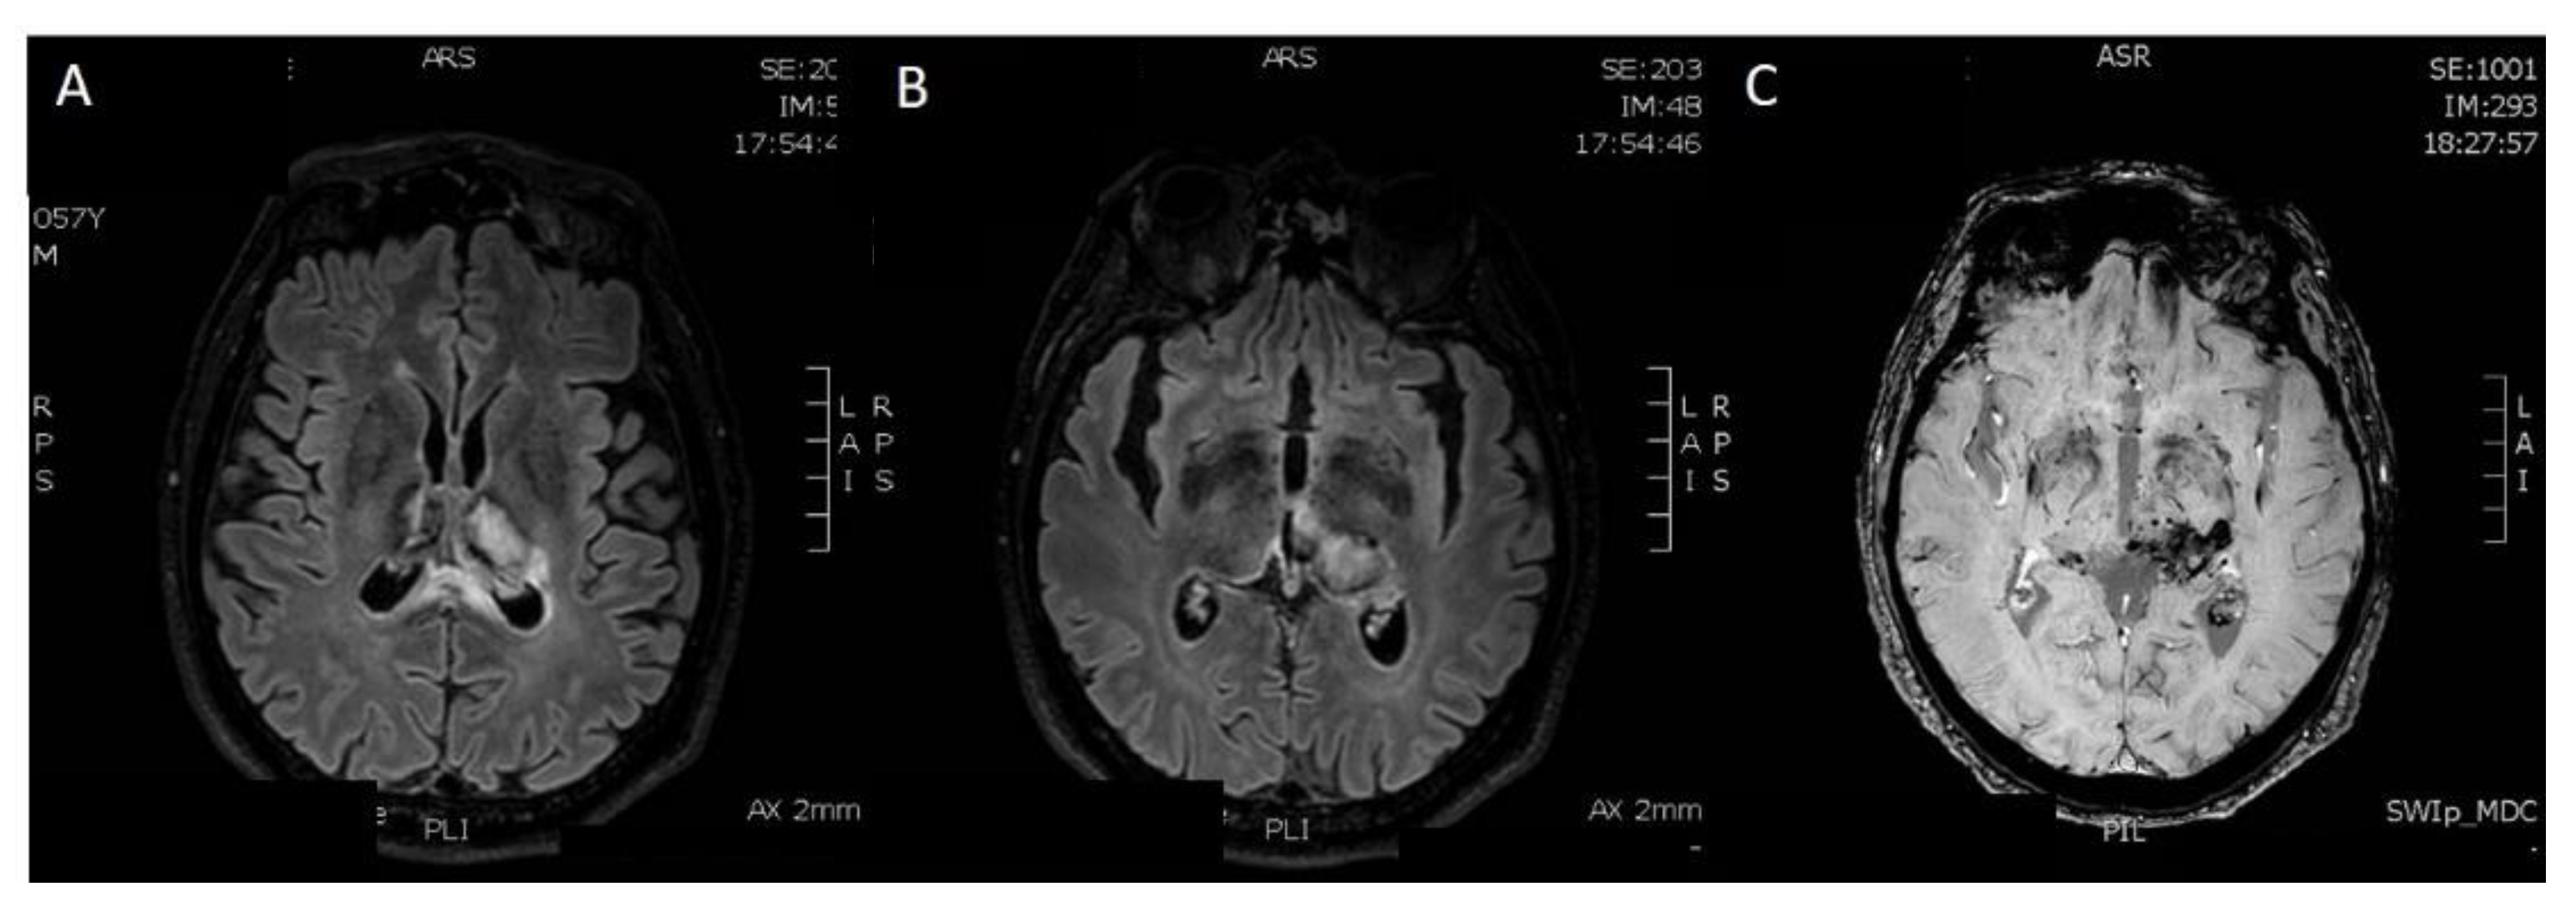

Brain MRI performed on a Philips Ingenia 3T MR system (Philips Healthcare, Best, The Netherlands), without medium contrast: (A) hyperintensity areas in both thalami (Axial T2-weighted image), (B,C) ischemic phenomena in thalami, left hippocampal and parahippocampal regions and haemorrhagic lesion in left parahippocampal region, view as hyperintense areas (Axial FLAIR-weighted images), (D,E) heavy metal deposits in the aforementioned regions (SWI, Susceptibility-Weighted Images), (F) ischemic lesion in the central portion of splenium of the corpus callosum (Sagittal FLAIR-weighted image). MRI was the first exam performed on the patient, a 56-year-old man who was hospitalized in July 2021 for severe asthenia, headache and acute confusional state, which started about 15 days after the first dose of Pfizer vaccine. The MRI sequences aforementioned allowed us to diagnose a subacute ischemic stroke. Chest X-ray, electrocardiogram and routine blood tests gave a negative response, except for high glycemic values (82 mmol/mol) and low platelets values (88 × 10−9/L) compared to the usual, normal patient’s platelet count. Genetic screening for coagulation disorders was negative.